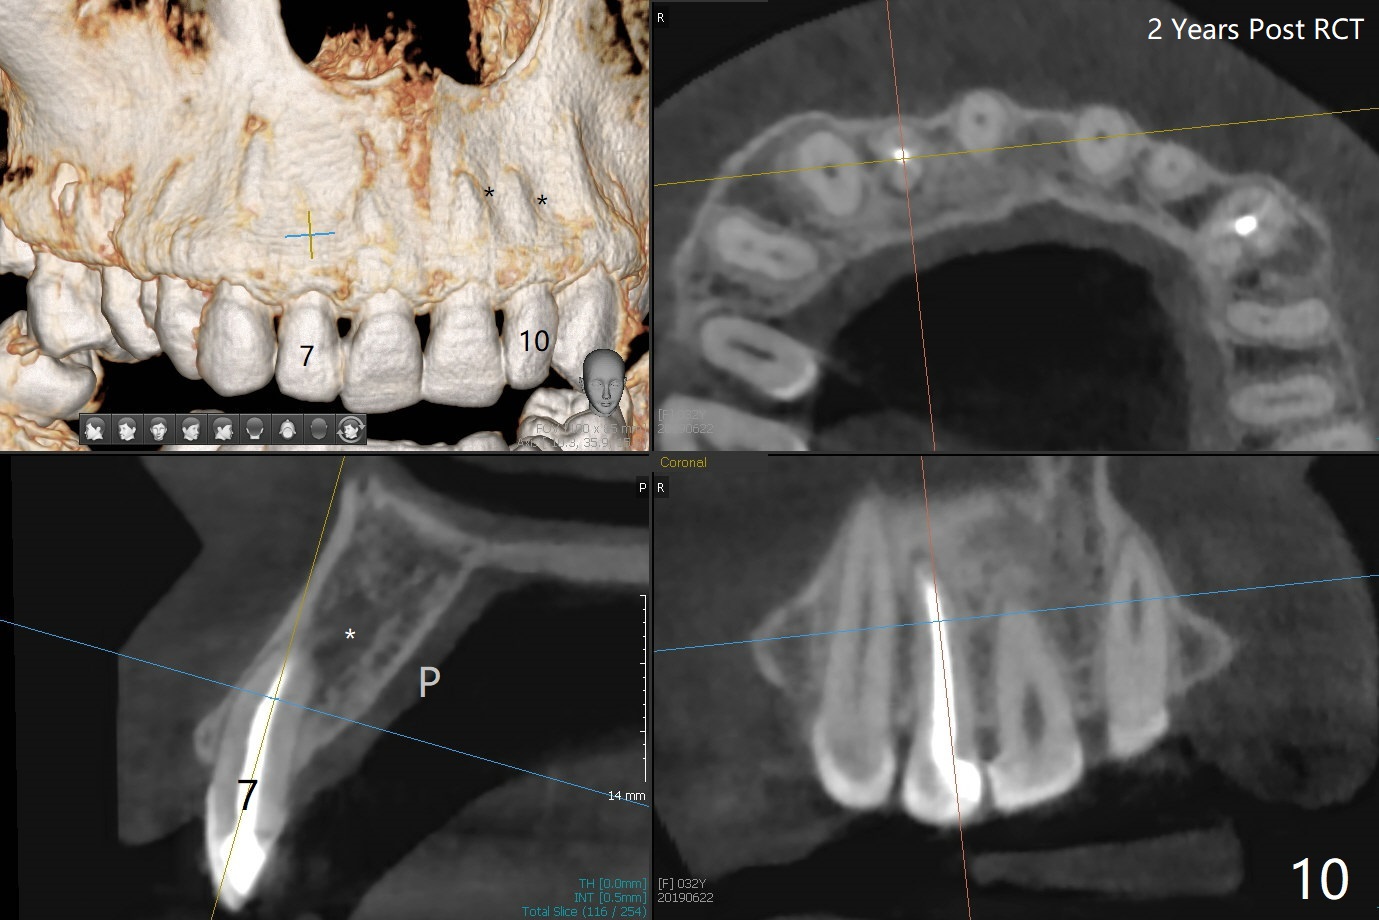

When this patient returns with improvement of symptoms, RCT will be finished. In fact the swelling relapses a month later (Fig.6). After discussion of possible cyst enucleation and increase in debridement from 30/.04 to 40/.06, a master cone of 40/.06 is inserted (Fig.7) and RCT is finished (Fig.8). Although the patient reports relapse of swelling, the palate looks normal and bone density increases 7 months postop (Fig.9). For 14 implant placement, CT is taken 2 years 1 month post RCT (Fig.10,11). Radiolucency is confined to the apex of the tooth #7 (white *). The labial concavities mesial and distal to the left lateral incisor makes radiolucencies (bone loss) look more radiolucent, creating globumaxillary cyst image. The globumaxillary cyst is a terminology for its shape. It does not mean congenital in nature. The treatment is dependent upon vitality test of the involved teeth.